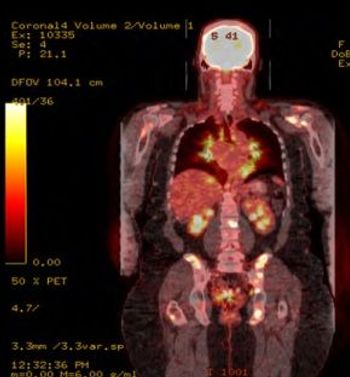

A 56-year-old woman presents with a history of intermittent shoulder pain for the past six months. Early signs point to bursitis, but the plot thickens: She also has sarcoidosis and lymphoma. How would you proceed?